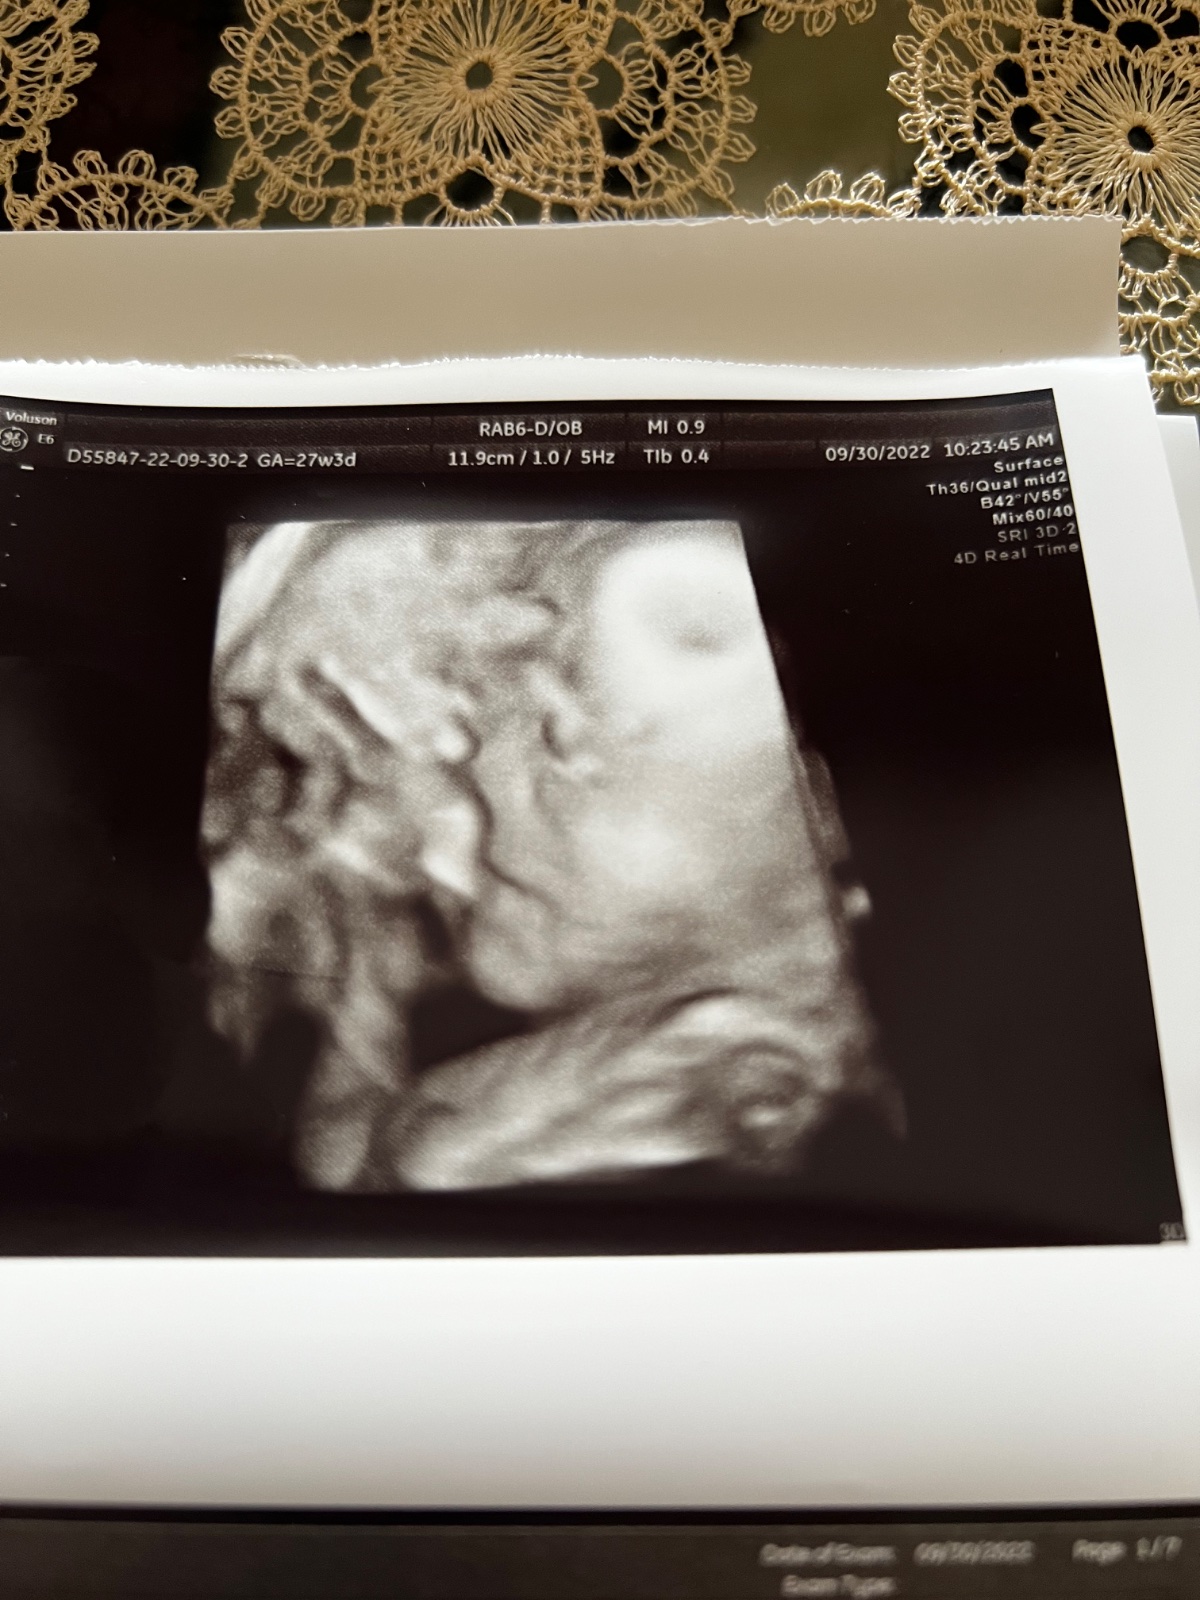

Zdravím, včera jsem byla na 4D ultrazvuku. Jsem v 28.týdnu, vzhledem k tomu, že mám placentu na přední straně, tak ten obraz nebyl nejlepší.

Prý má 1kg. Přijde Vám, že je na svoje ,,stáří” dost malinký? Na 4D ultrazvuku jsme byla poprvé a nevím ,jak moc tedy obraz odpovídá realitě. Podle obrázku to vypadá, že prakticky nemá žadné rtíčky.😅